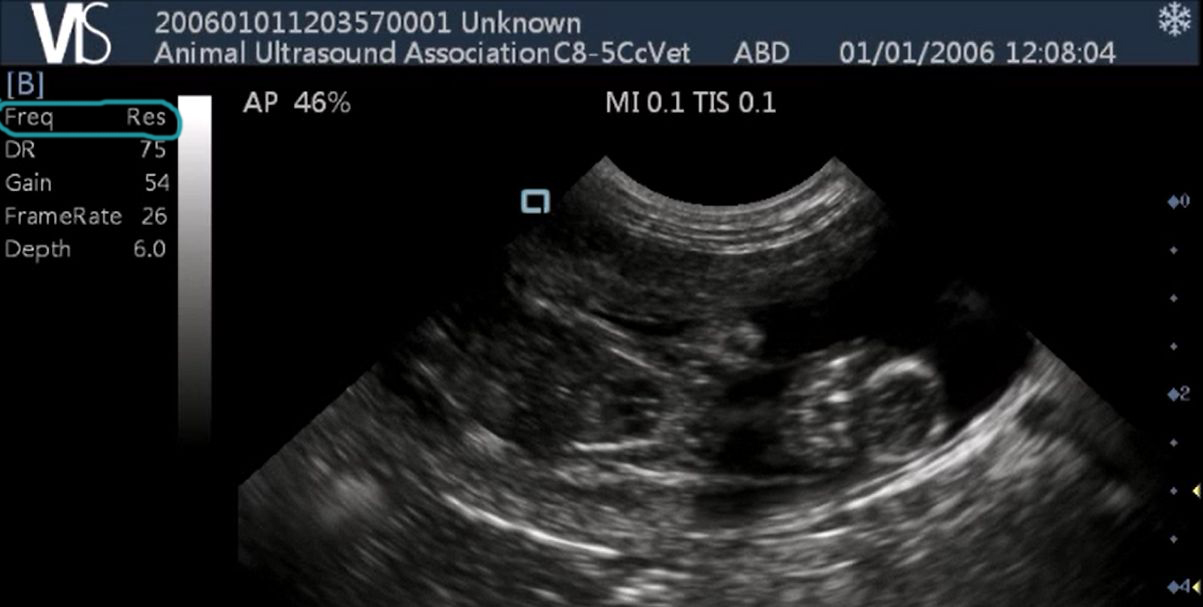

Below are some examples of scan images taken at higher frequencies. The scanning frequency has been circled in blue. The below images are captured at high resolution.

High resolution Scan Pad image

High resolution Scan Pad canine scan